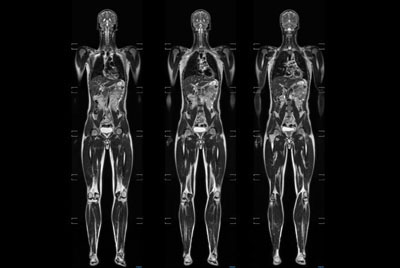

Whole Body imaging under 30 minutes on BlueSeal magnet

Whole Body imaging

Total Body Imaging